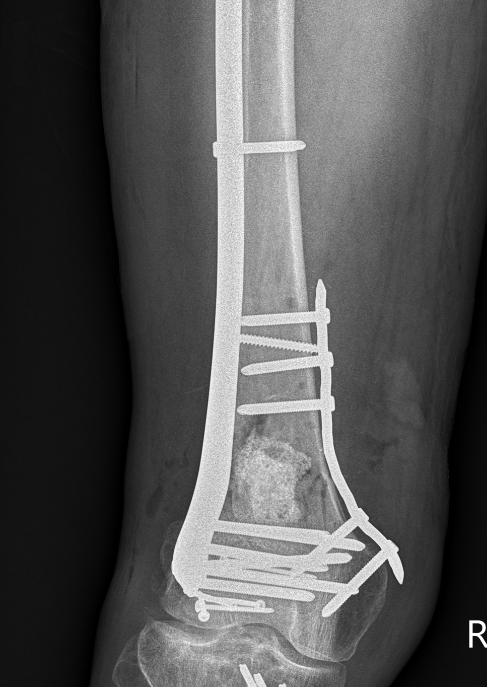

Type C: Complete articular

Xray / CT

Options

Dual Plate

Plate + Retrograde nail

Distal femur replacement

Indications

Significant comminution

Loss of medial cortical buttress